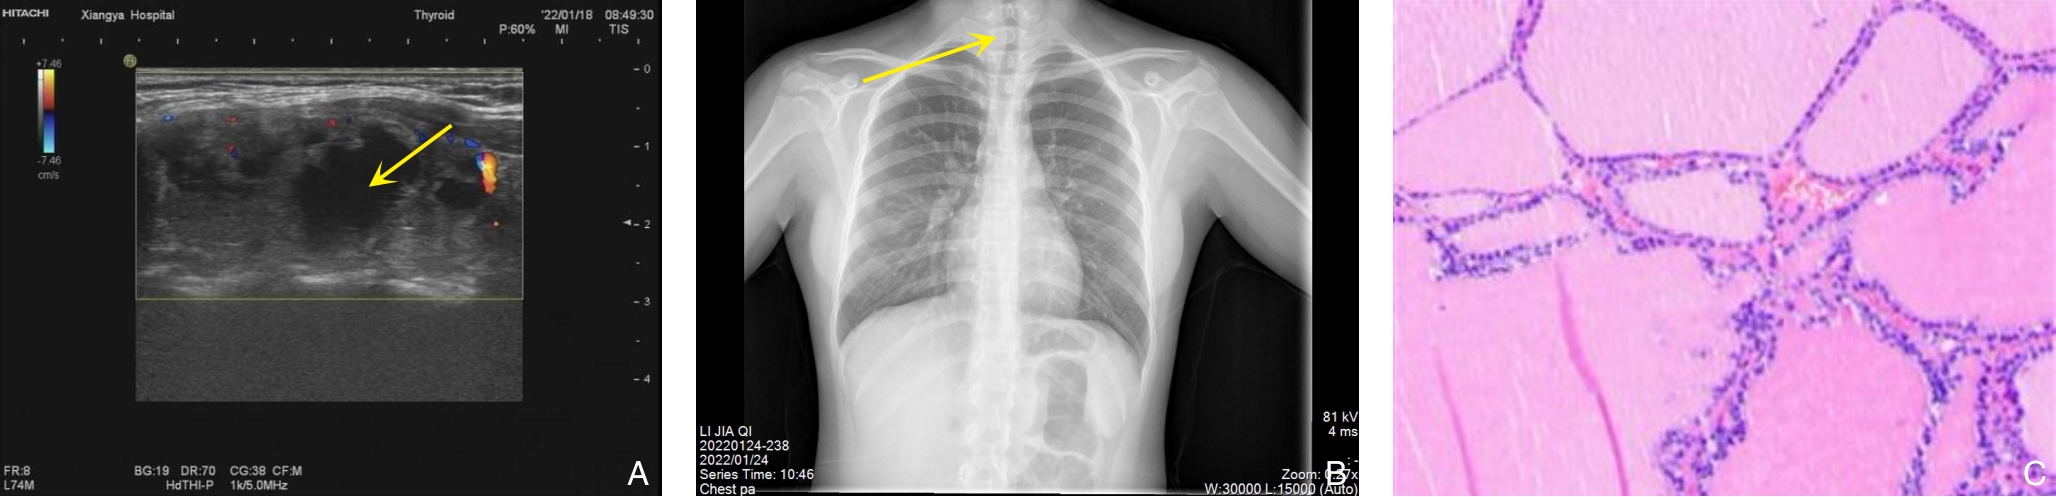

• China Journal of General Surgery, 2026, 35(1):180-186.

2026, 35(1):180-186. DOI: 10.7659/j.issn.1005-6947.250293

Abstract (80) HTML (146) PDF 1.36 M (161) Comment (0) Favorites

Abstract:背景与目的 DICER1综合征是一种由DICER1基因胚系突变引起的罕见常染色体显性遗传性肿瘤易感综合征,可累及多器官并表现为多种良恶性肿瘤或增生性病变。肾外肾母细胞瘤、多结节性甲状腺肿及Sertoli-Leydig(S-L)细胞瘤均为其相关表型,但三者同时出现的病例尚未见报道。本文报告1例同时合并上述三种表型的DICER1综合征患者,并结合文献进行分析,以提高对该综合征复杂临床谱系的认识。方法 回顾性分析1例女性患者的临床资料,包括临床表现、影像学检查、手术经过、病理学及免疫组化结果、基因检测及家庭谱系图分析结果;同时检索并总结近30年相关文献,对具有肾母细胞瘤、结节性甲状腺肿及S-L细胞瘤等表型的DICER1综合征病例进行归纳分析。结果 患者9岁时因腹痛行右侧卵巢肿瘤切除术,病理诊断为原发性卵巢畸胎样肾外肾母细胞瘤,术后行辅助化疗。3年后因甲状腺结节行右侧甲状腺切除术,病理为多结节性甲状腺肿。半年后因左侧盆腔新发肿块行卵巢囊肿剥除术,病理提示低分化S-L细胞瘤。基因检测发现DICER1基因外显子8 c.904-1G>C杂合突变,其父亲为同位点杂合突变携带者。结合临床表现及分子遗传学结果,确诊为DICER1综合征。随访3年未见复发或新发病灶。文献复习显示,同时合并上述三种表型的病例尚未见报道。结论 DICER1综合征临床表型多样且诊断具有挑战性。当患儿出现多器官肿瘤或罕见肿瘤组合时,应警惕遗传性肿瘤综合征的可能,尽早开展基因检测及家系筛查。早期识别DICER1综合征对于制定个体化治疗策略及开展长期监测随访具有重要意义。

• 0+1

• 1+1

• 2+1

• 3+1